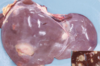

Hydatidosis

What is the cause of hydatidosis?

Intermediate stage of Echinococcus granulosa (dog tapeworm)